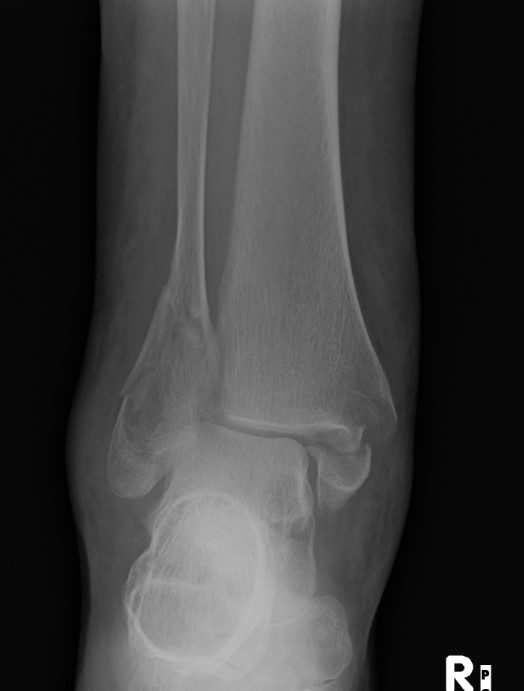

Poor bone

Poor wound healing

Poor union rates

ORIF

- poor bone stock

- wound issues

Indications

Fragility fracture / osteoporosis

Compound wound

Poor skin

Co-morbidities - diabetes, smoking